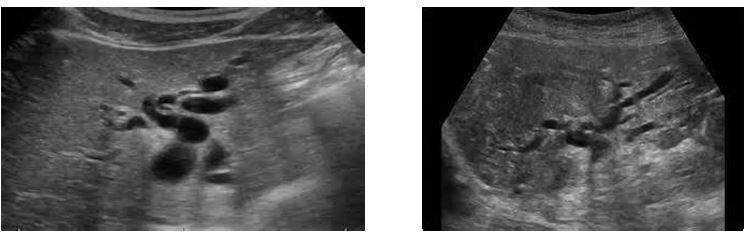

different patterns of cholelithiasis

what is this showing

Cholelithiasis w Floating Stones

Cholelithiasis showing multiple small floating and

nonfloating gallstones